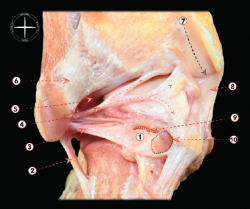

Figura 1. Visión anterolateral de una disección osteoarticular del tobillo. 1: ligamento tibiofibular anterior (y fascículo distal); 2: ligamento talofibular anterior; 3: tendón calcáneo; 4: ligamento calcaneofibular; 5: inserción del tendón del peroneo tercero; 6: tendón del peroneo largo; 7: ligamento talonavicular dorsal; 8: ligamento cervical; 9: parte anterior del ligamento deltoideo. Figura cedida por el Dr. Miki Dalmau-Pastor, publicada en “Anatomía del tobillo” en este mismo monográfico.

1. El complejo ligamentoso lateral, que se compone, a su vez, del ligamento peroneo-astragalino anterior (LPAA), el ligamento peroneo-calcáneo (LPC) y el ligamento peroneo-astragalino posterior (LPAP). El LPAA se origina en el aspecto anterior del peroné distal y se inserta en el cuerpo talar justo delante de su faceta articular, siendo confluente con la cápsula lateral (Figura 1). El LPC se origina distalmente al origen del LPAA y se inserta en el calcáneo (Figura 1). El LPAP se origina en el aspecto posteromedial del maléolo lateral y tiene una amplia inserción en la zona posterior del calcáneo(2)(Figura 2).

Figura 2. Visión posterior de una disección osteoarticular del tobillo y la articulación subtalar. 1: os trigonum; 2: ligamento calcaneofibular; 3: ligamento talofibular posterior; 4: ligamento intermaleolar; 5: componente profundo del ligamento tibiofibular posterior (ligamento transverso); 6: componente superficial del ligamento tibiofibular posterior; 7: surco para el tendón del tibial posterior; 8: parte posterior del ligamento deltoideo; 9: rotura de la sincondrosis entre un os trigonum y el cuerpo del astrágalo; 10: túnel osteofibroso para el flexor largo del primer dedo. Figura cedida por el Dr. Miki Dalmau-Pastor, publicada en “Anatomía del tobillo” en este mismo monográfico.